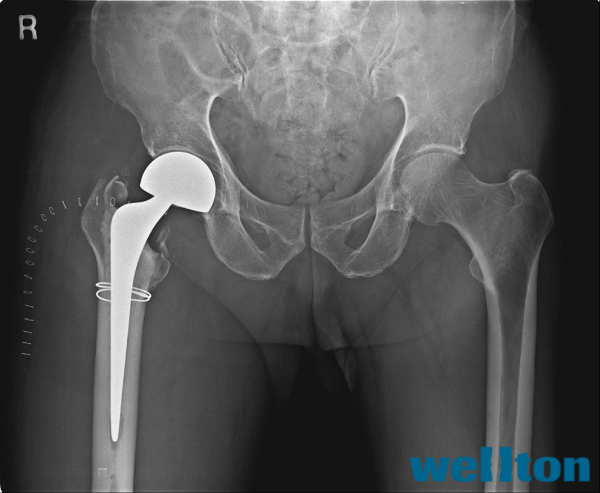

5. 치료의 선택: 왜 인공관절인가?

핀으로 고정하는 '내고정술'은 본래의 뼈를 살린다는 장점이 있으나, 고령 환자에겐 뼈가 붙을 때까지 수개월간 침대에서 지내야 한다는 치명적인 단점이 있습니다.

반면, 인공관절치환술(시멘트형)은 다음과 같은 이점이 있습니다.

- 즉각적인 안정성: 골 시멘트(바이오 접착제)를 이용한 단단한 고정으로 뼈가 붙는 기간 없이 즉시 체중 부하가 가능합니다.

- 근육 보존 기술: 외회전근을 자르지 않고 보존하여 탈구 위험을 최소화합니다.

- 조기 보행: 뼈가 붙길 기다릴 필요 없이 수술 직후 재활을 시작해 내과적 합병증을 원천 차단합니다.

5. Choosing the Treatment: Why Artificial Joint Replacement?

Internal Fixation (pinning) has the advantage of preserving the natural bone, but it has a fatal downside for elderly patients: they must remain in bed for months until the bone heals.

In contrast, Artificial Joint Replacement (Cemented Type) offers the following benefits:

- Immediate Stability: The use of bone cement (bio-adhesive) provides firm fixation, allowing for immediate weight-bearing without waiting for the bone to knit.

- Muscle Preservation Technique: By preserving the external rotator muscles rather than cutting them, the risk of dislocation is minimized.

- Early Ambulation: Rehabilitation can start immediately after surgery without waiting for the bone to heal, effectively blocking internal medical complications.